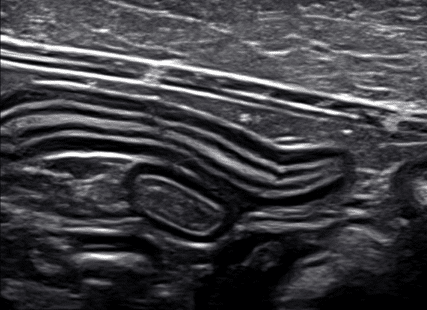

Examples of diffuse small intestinal diseases include non-specific enteritis, inflammatory bowel disease, or infiltrative neoplasia such as lymphoma. Both inflammatory bowel disease and lymphoma can have a normal appearance of the small intestine on ultrasound or demonstrate a thick muscularis layer described as muscularis to submucosa ratio of greater than one (Figure 2a-2c). Cats with lymphoma are more likely to present with a thick muscularis layer, while approximately 20% of dogs with lymphoma can have a normal small intestinal wall on ultrasound. In dogs, inflammatory bowel disease can be seen as segmental or diffuse muscularis thickening. Enlarged, rounded, hypoechoic lymph nodes are more often present with lymphoma. They can be a way to obtain a diagnosis via fine needle aspiration without requiring a small intestine biopsy. If the cytology does not clearly indicate round cell neoplasia or the lymph nodes are only mildly enlarged or normal, a biopsy of the small intestine (via endoscopy or exploratory laparotomy) would be required for a definitive diagnosis due to the large overlap in the appearance between the two diseases.

Figure 2b (above): Example of a normal small intestinal wall on ultrasound.

Figure 2c (above): Example of a thick muscularis layer of the small intestinal wall as seen with inflammatory bowel disease and lymphoma.